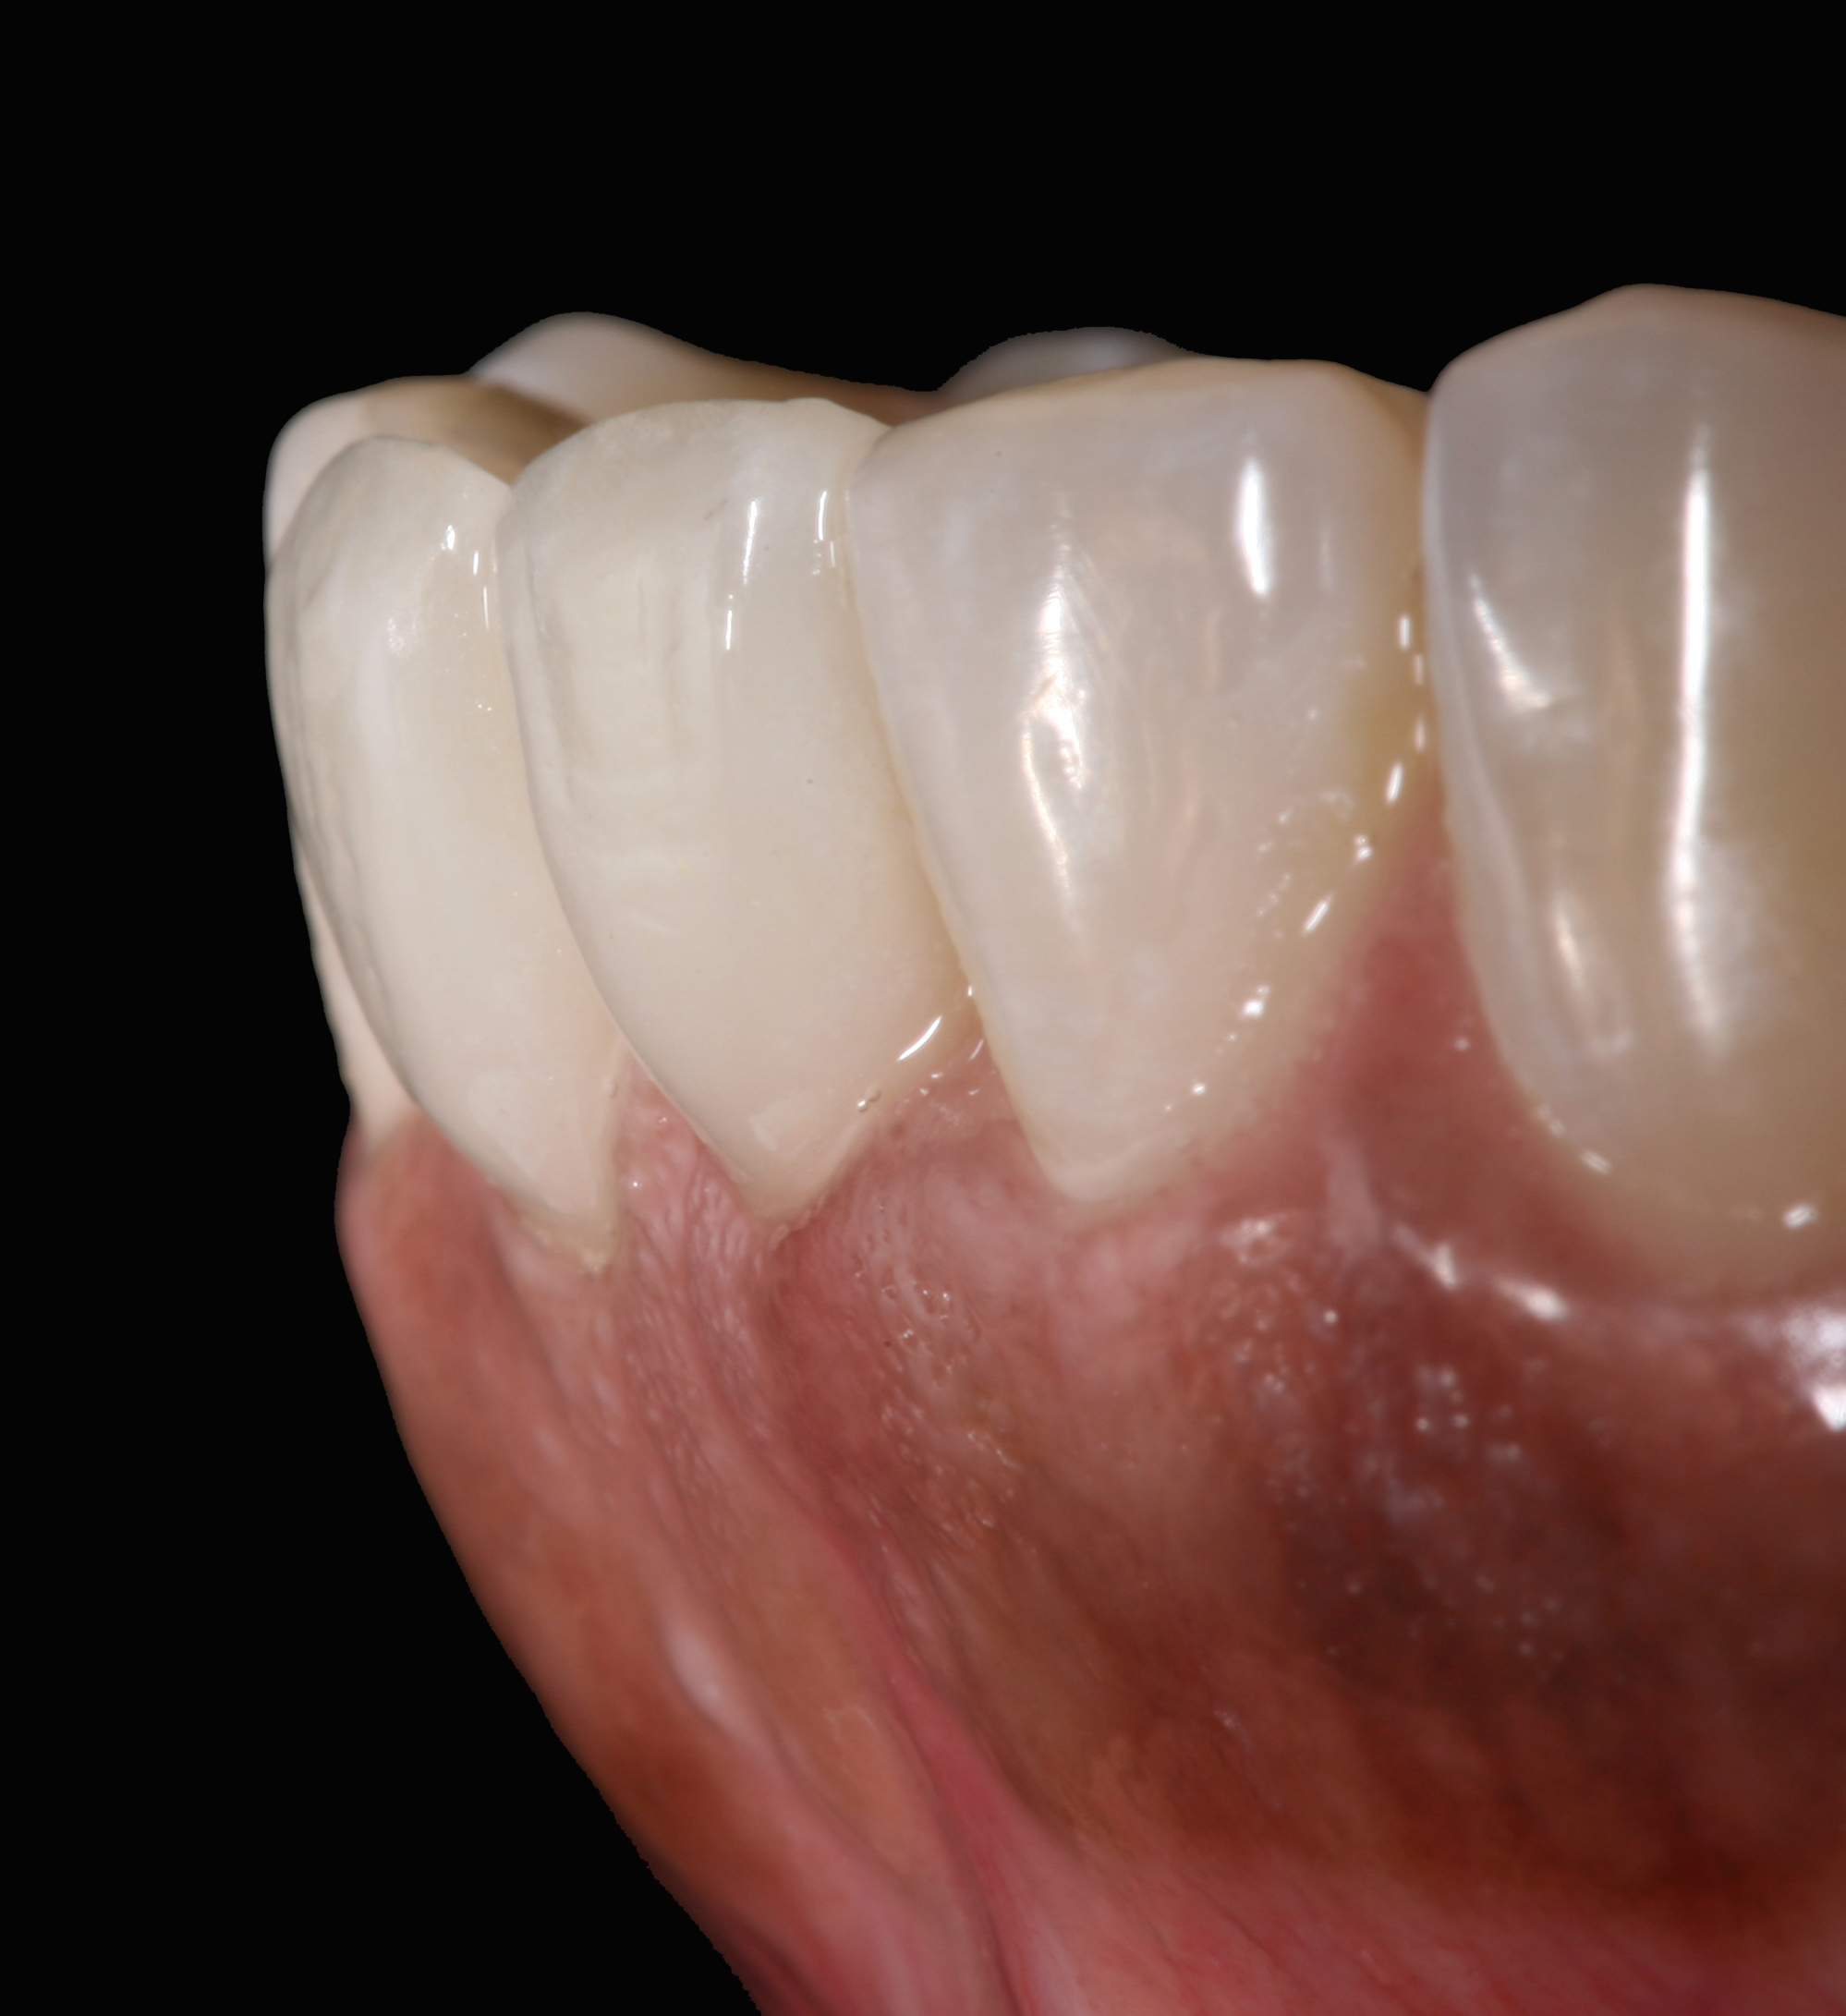

Postoperative situation: left lateral view.

Figure 11